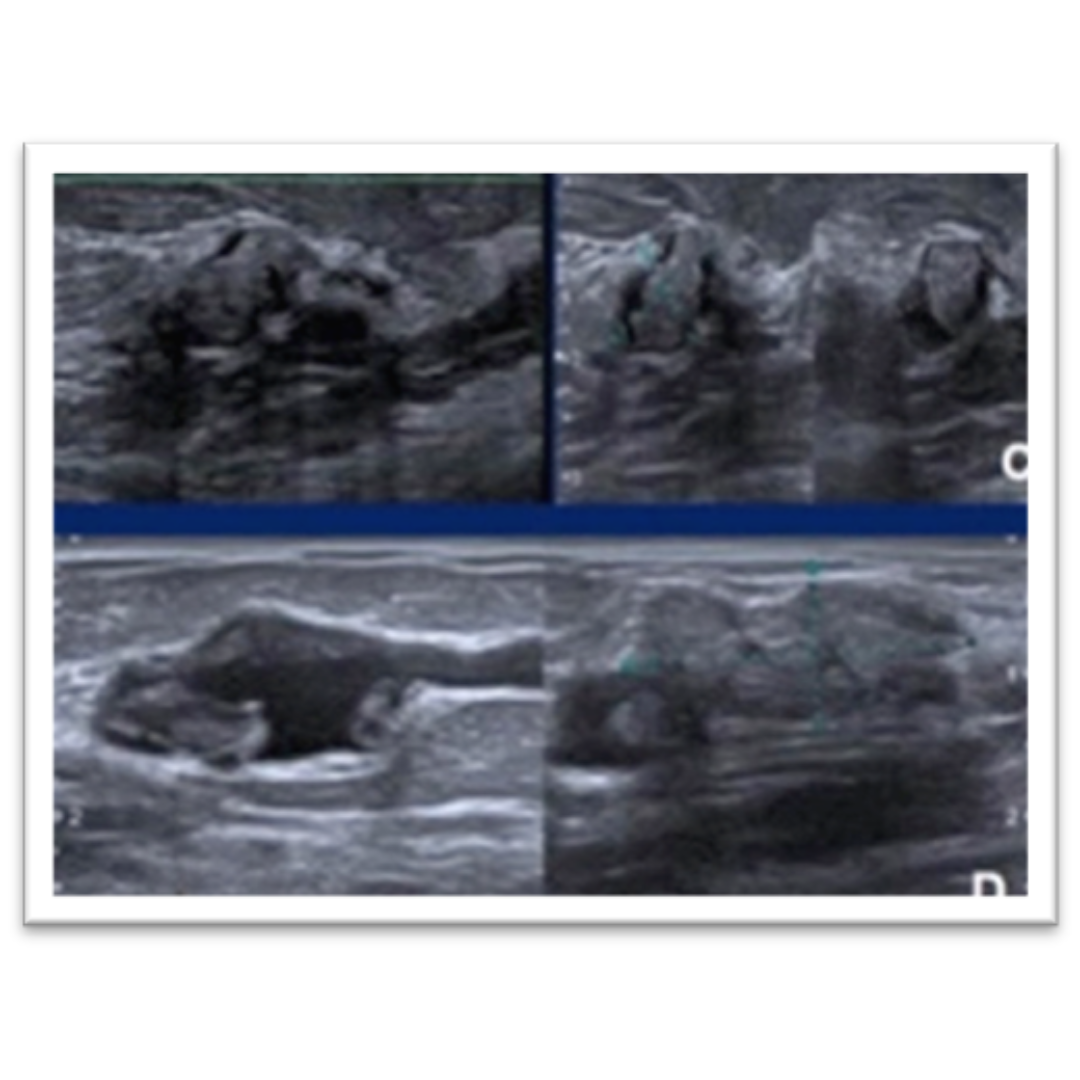

Diagnósticos Diferenciales Ecográficos de Quistes Epidérmicos